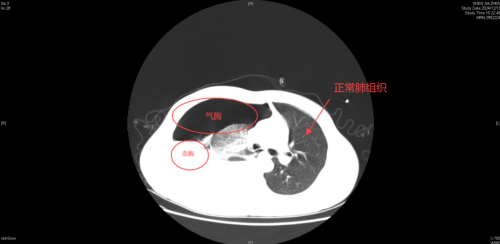

急诊科接诊医生苏英杰发现患者面唇苍白,呈贫血貌,听诊其肺右侧呼吸音消失,随后的影像资料提示右侧液气胸,且压缩肺组织达到了75%,情况极为凶险。

CT影像示右侧液气胸,压缩肺组织达到了75%